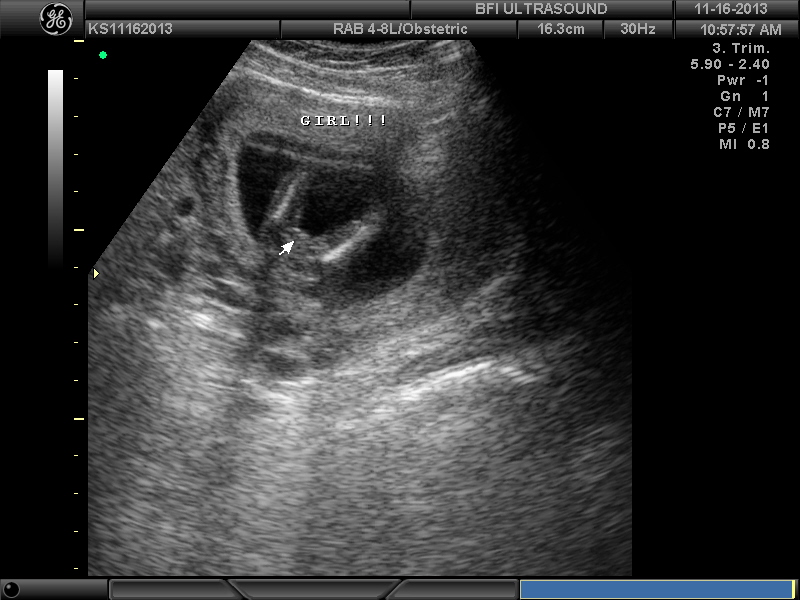

BFP#4 8.27.13 (EDD 5.6.14) DD born 4.23.14